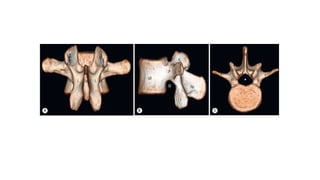

This three-dimensional reconstruction from computed tomography (CT) axial images focuses on the occipital–

cervical junction and the C1-2 (atlantoaxial) junction

The skull base has been cut away nearly completely in this

CT model, allowing the ring of C1 and its relationship to the

dens of C2 to be seen in detail.

C1 and C2 view of the normal cervical spine

This three-dimensional CT model is oriented with the observer looking cephalad along the anterior

surface of the cervical spine. A series of holes perforating the transverse processes of each vertebra

can be seen—the transverse foramen.

This three-dimensional reconstructionfrom computed tomography (CT) axial images focuses on the occipital– cervical junction and the C1-2 (atlantoaxial) junction

The skull basehas been cut away nearly completely in this CT model, allowing the ring of C1 and its relationship to the dens of C2 to be seen in detail. C1 and C2 view of the normal cervical spine

This three-dimensional CTmodel is oriented with the observer looking cephalad along the anterior surface of the cervical spine. A series of holes perforating the transverse processes of each vertebra can be seen—the transverse foramen.